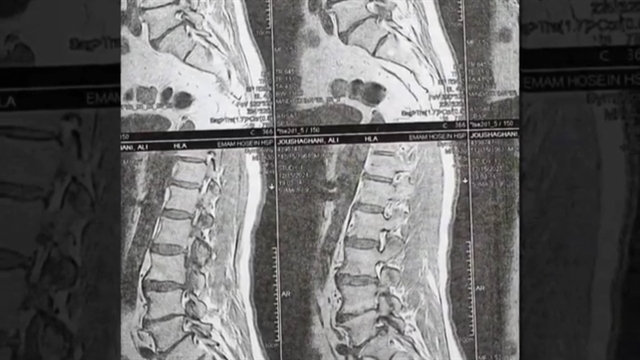

آقای 60 ساله با درد شدید کمری